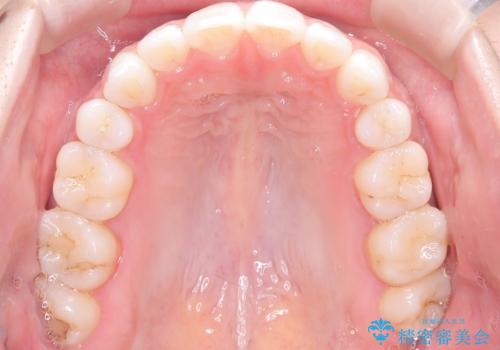

- 患者さんは「口元を引っ込めたい」「八重歯をきれいにしたい」とのご希望で来院されました。診察の結果、上下の前歯が前方に傾斜し、口元がやや突出して見える状態でした。加えて、上顎には八重歯があり、歯列のスペース不足も確認されました。

歯並びと横顔のバランスを整えるためには、前歯を後方に移動させるスペースの確保が必要です。そのため、上下左右の第一小臼歯(合計4本)を抜歯し、ワイヤー矯正で前歯の突出感と叢生(がたつき)を同時に改善する治療計画を立てました。歯を抜くことに抵抗がある方も多いですが、口元の印象を変えるためには非常に効果的な方法です。

上下左右の小臼歯を抜歯後、ワイヤー矯正装置を装着し、全体のバランスを見ながら歯を移動させていきました。特に前歯の後方移動では、抜歯スペースを活かして口元を内側に下げることに重点を置きました。また、八重歯も時間をかけて丁寧に整列させ、左右の正中(真ん中の位置)もぴったりと揃えることができました。

治療期間は約2年で、歯並びだけでなく横顔の印象も大きく改善されました。治療後には「口元がすっきりして笑顔に自信が持てるようになった」とのお声をいただきました。現在は後戻りを防ぐため、保定装置(リテーナー)を使用しながら経過観察中です。ワイヤー矯正は審美性と機能性を両立できる有効な選択肢の一つです。